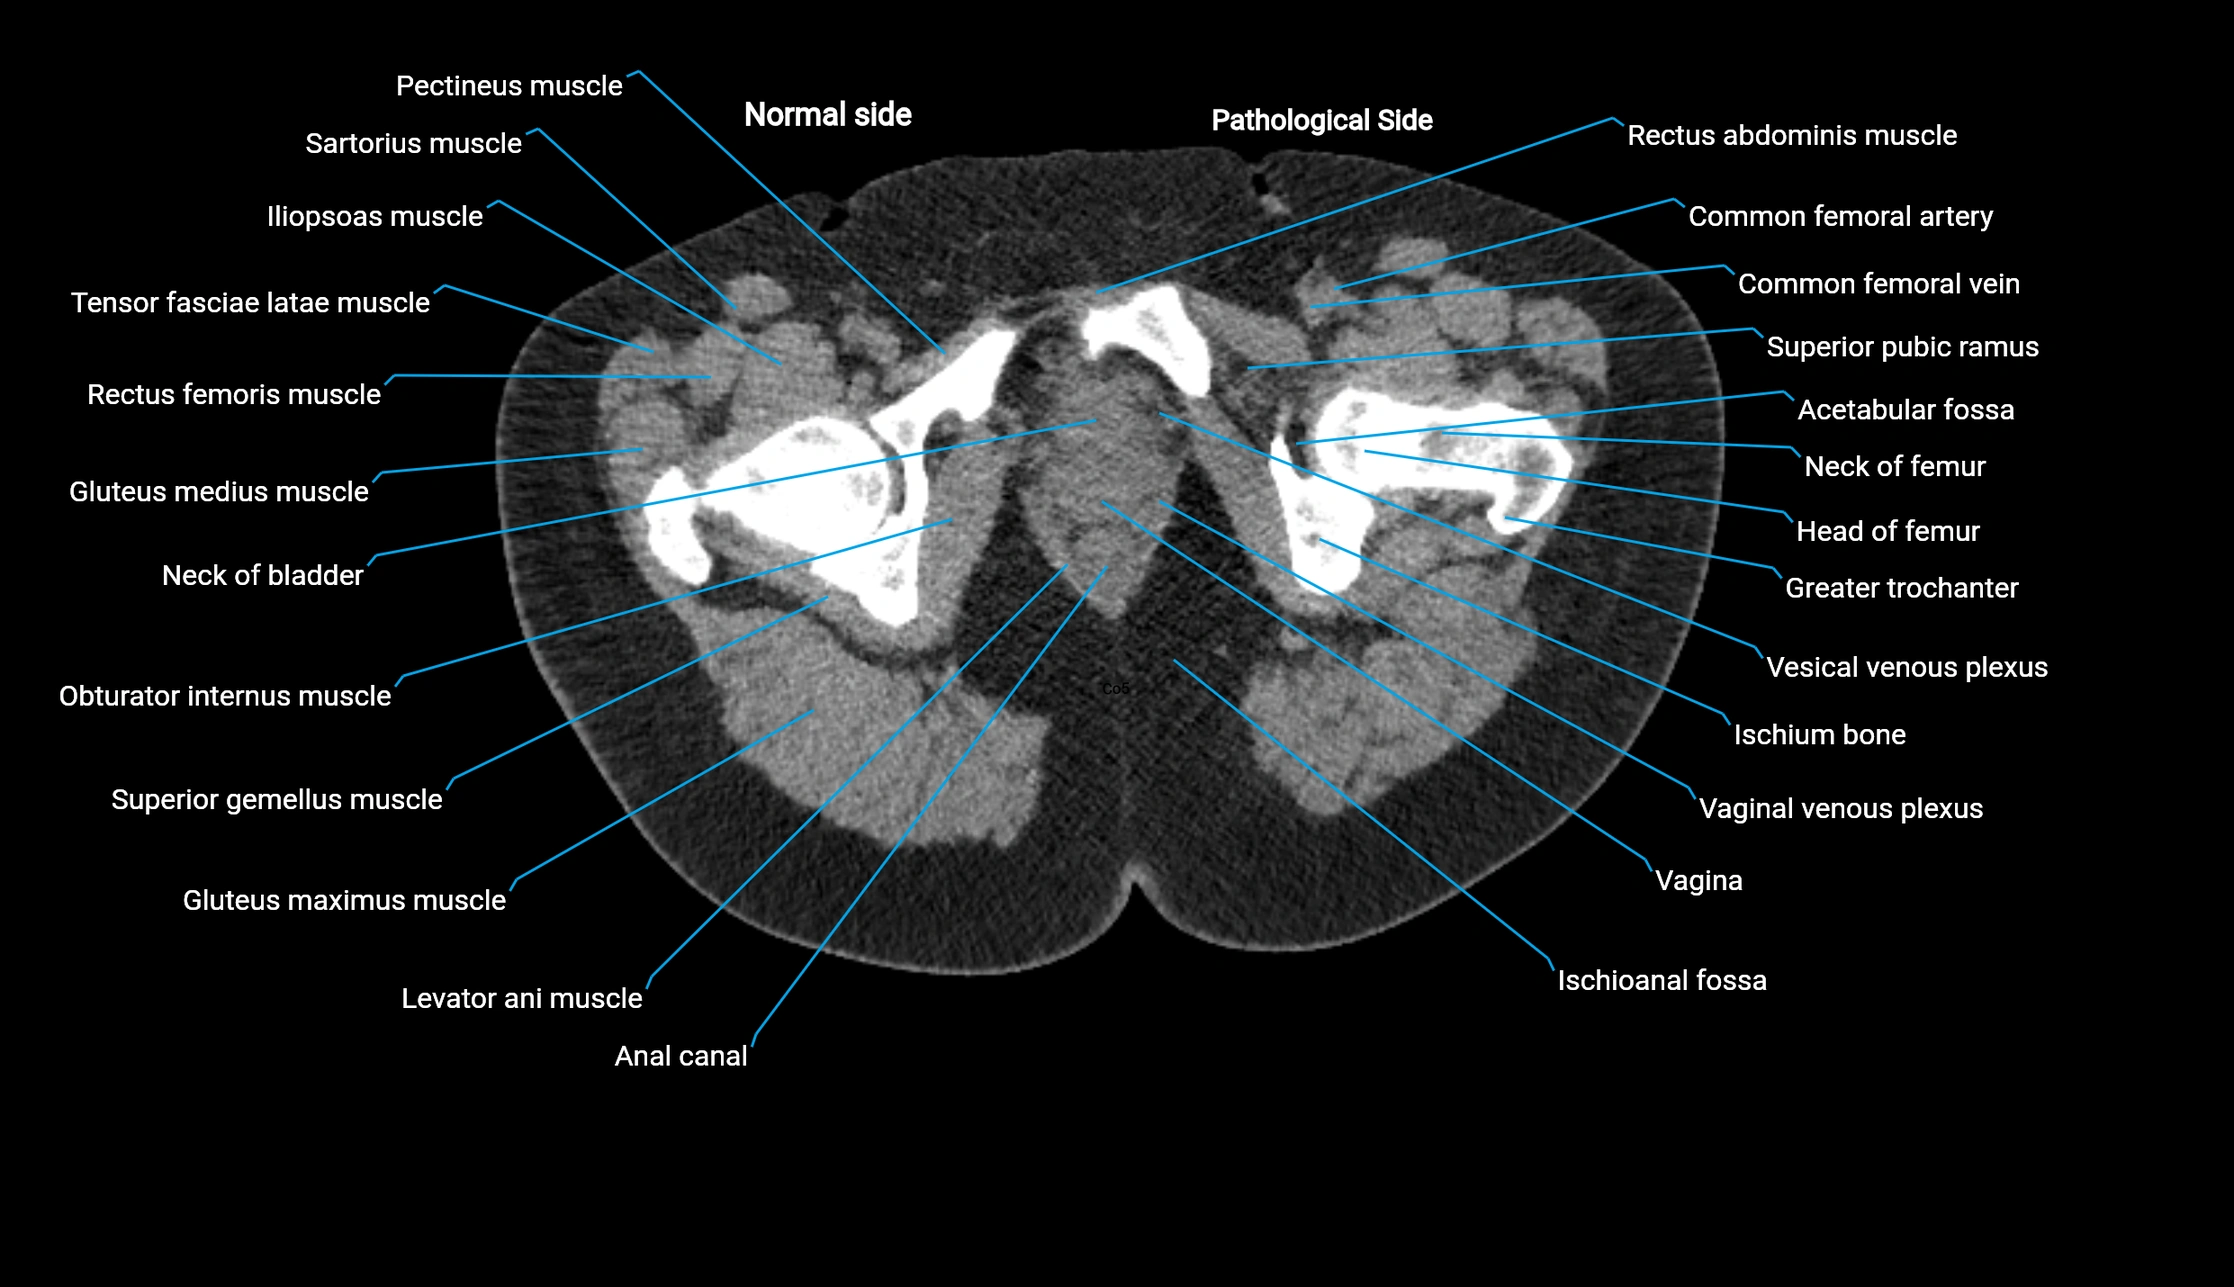

CT image

image